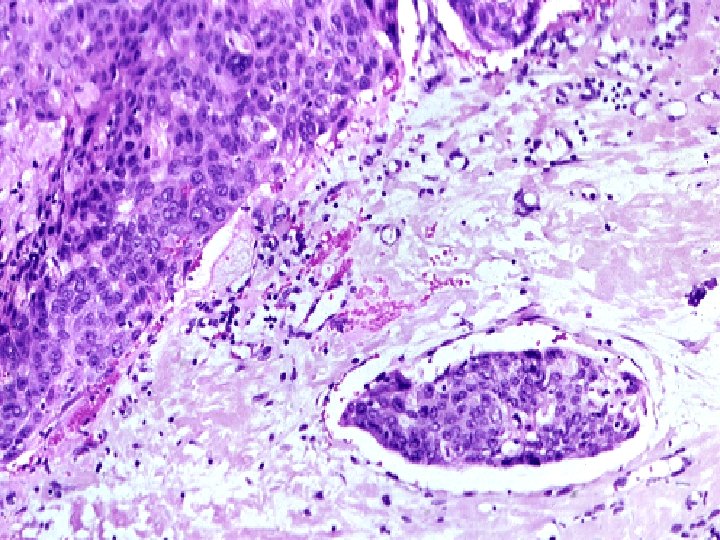

A, Carcinoma of the cervix, well advanced. B, Early stromal invasion occurring in a cervical intraepithelial neoplasm

Cervical Carcinoma (invasive carcinoma), Morphology Mainly in the region of the transformation zone, and range from microscopic foci of early stromal invasion to grossly frank tumors encircling the cervical Os. The tumors may be invisible or exophytic. Cervical carcinomas are graded from 1 to 3( i. e. well, moderately and poorly differentiated) based on cellular differentiation and staged from 1 to 4 depending on clinical spread.